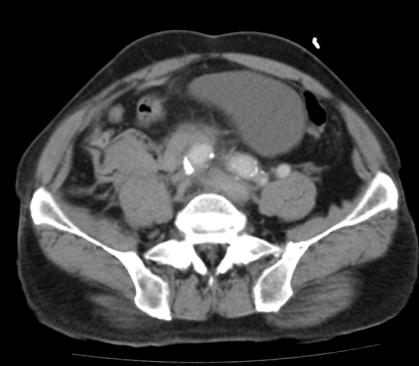

增强后:腹主动脉下段至左右髂总动脉上端明显扩张,最宽处约6.8cm,上下径约为13cm,成瘤样改变,边界清楚,形态规整。

膀胱充盈良好,膀胱壁无明显增厚。